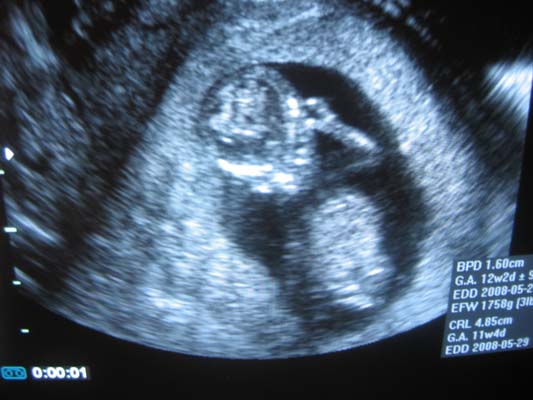

Kép Ime a kis vasgyúró 12 hetesen aki éppen integetett!:):):)

Lehet hogy kicsi lett és nem láttok majd semmit,de megprobálom azért!

Tök jó az uh kép :D

Friss kép nincs?

Nekem hétfőn csináltak de,csak egy pötyike látszik rajta.

No meg hasi uh-t csinál a dokim,és azon nem látszik olyan jól de,a lényeg hohy ott van :D